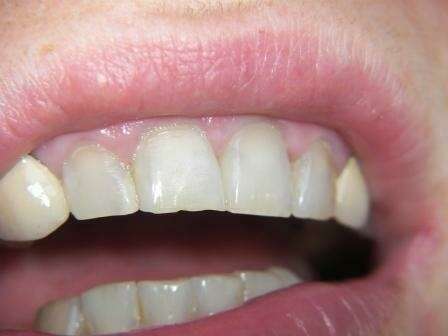

Lorsqu'une couronne choque par sa couleur et qu'il n'y a pas de solution satisfaisante pour la patiente.